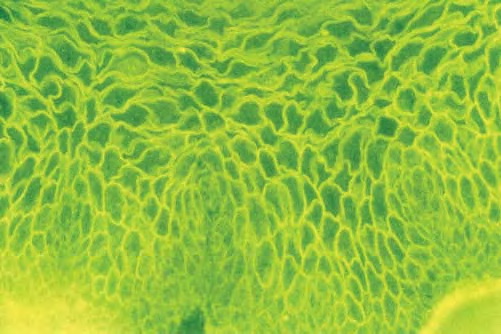

Parapsoriasis Large-plaque = نظير الصدف كبير اللويحات Parapsoriasis There are three entities described as parapsoriasis: small-plaque parapsoriasis, large-plaque parapsoriasis, and parapsoriasis variegata. Large-plaque parapsoriasis and parapsoriasis variegata are best considered as early stages of cutaneous T-cell lymphoma/mycosis fungoides. The small-plaque parapsoriasis is also known as xanthoerythrodermia perstans of Crocker and as digitate dermatosis . Pink-to-yellow, slightly scaly, oval or elongated, […]